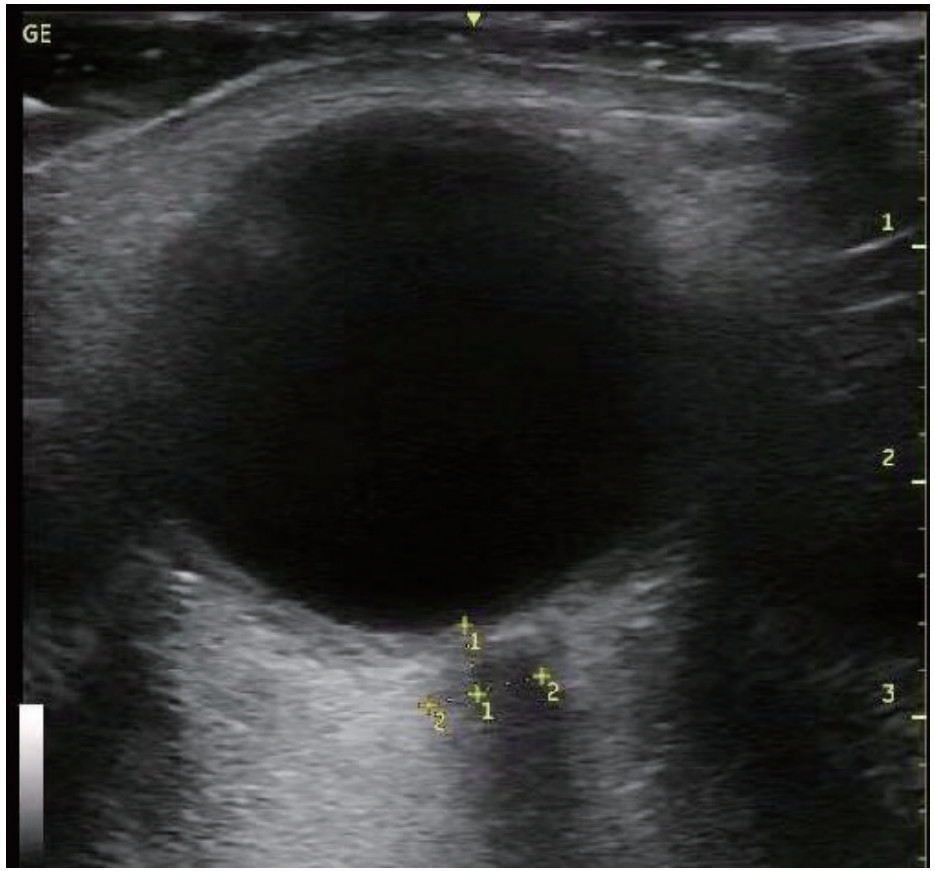

1.2 方法 1.2.1 资料收集通过查阅电子病历收集CCS患者年龄、性别、是否合并高血压和(或)糖尿病等基础病、急诊入院时头颅CT影像学表现、GCS评分、急性生理学与慢性健康状况评分Ⅱ(APACHE Ⅱ)等基本资料,以及急诊入院后电解质(钾、钠),血液检查指标C反应蛋白(CRP)、葡萄糖(GLU)、肌酸激酶(CK)、肌酸磷酸激酶同工酶(CKMB)、乳酸脱氢酶(LDH)、神经元特异度烯醇化酶(NSE),手术后转入ICU监测床边心脏彩超指标:速度时间积分(VTI)(见图 1)、射血分数(EF),右心Tei指数,术后颅内压(ICP)及相应时间的视神经鞘直径(ONSD),记录术后第3天ICP,并计算ICP变化率=(术后ICP-术后第3天ICP)/术后ICP等临床资料,记录两组患者转入ICU是否使用血管活性药物及用量(重酒石酸去甲肾上腺素注射液生产厂家:远大医药(中国)有限公司,批准文号:国药准字H42021301,规格:2 mg/支),镇静镇痛等治疗用量及平均每日液体平衡量等指标,其中镇痛药物使用注射用盐酸瑞芬太尼(生产厂家:宜昌人福药业有限责任,批准文号:国药准字H20030197,规格:1 mg/瓶),镇静药物为丙泊酚注射液(生产厂家:西安力邦制药有限公司,批准文号:国药准字H19990282,规格0.2 g/支)。心脏彩超及ONSD测量均为本院通过重症超声规范化培训并取得合格证书者完成,心脏彩超测量采用EDGE型彩色多普勒超声仪(美国索诺声公司)检测,其中Tei指数是由多普勒超声衍生而出的时间间期指数,定义为等容收缩时间(ICT)与等容舒张时间(IRT)之和除以射血时间(ET)。Tei指数的计算公式:Tei指数=(ICT+IRT)/ET。连续测量3次取平均数。ONSD采用EDGE型彩色多普勒超声仪(美国索诺声公司)高频(5.0~10.5 MHz)线阵超声探头测量眼球后3 mm位置视神经鞘的宽度,并反复测量3次取平均值(见图 2)。

| 图 2 超声下视神经鞘直径测量(ONSD) Fig 2 Measurement of optic nerve sheath diameter under ultrasound (ONSD) |